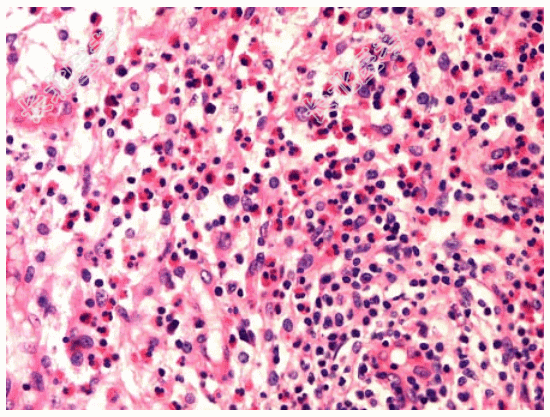

- [材料题] 患者男性,53岁,腹胀,返酸,嗳气半年。胃镜检查见胃窦部黏膜稍粗糙,并可见小片状糜烂。

- 简答题1、镜检如图所示黏膜内大量炎细胞浸润,以哪一类炎细胞为主?

- 简答题2、综合所见,正确的诊断为?